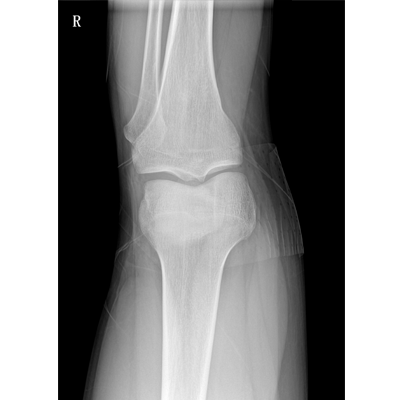

輕量化設(shè)計(jì) 小巧靈活 PLX5100

用于影像科、急診室、病房、ICU、手術(shù)室等多場(chǎng)景應(yīng)用。

● 數(shù)字化無(wú)線平板成像,操作簡(jiǎn)便,成像質(zhì)量高